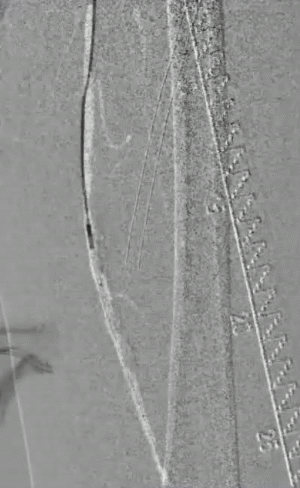

术前造影:右侧股浅动脉中段重度狭窄、远端闭塞,膝下仅腓动脉通畅。

图片图片图片

手术策略:DA+DCB